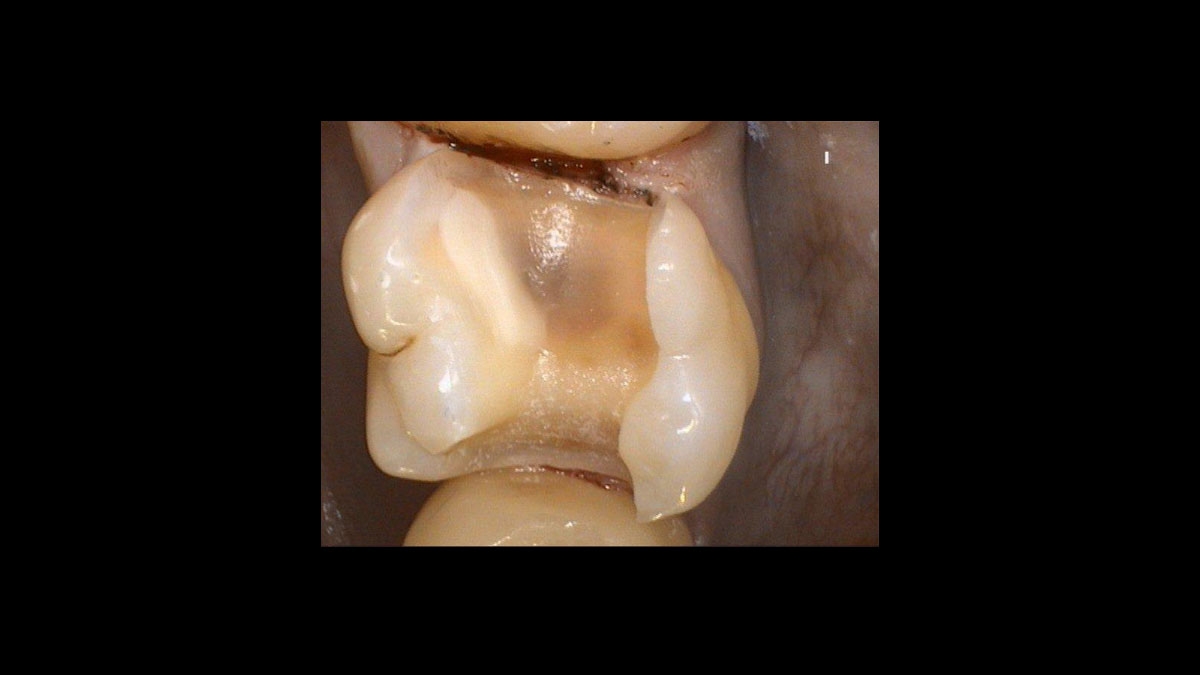

Zub 16 po preparaci

Po hemostáze